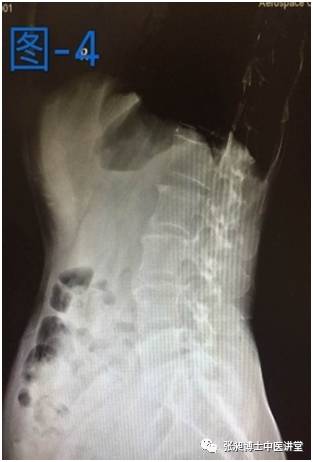

当时这位阿姨主要临床表现:腰痛,伴右下肢大腿外侧疼痛,疼痛不过膝盖。右侧臀部疼痛,范围局限,右侧强迫体位,无法弯腰,弯腰时右侧腰部酸痛。下图是当时做的影像学检查。患者很是痛苦,腰椎侧弯已经严重影响患者生活。张昶医生建议患者小针刀治疗。

后来这位患者经过两个月的小针刀治疗后疼痛缓解,右侧强迫体位缓解,生活质量也得到很大提高。腰椎侧弯也好转,如下图所示,是患者治疗前和治疗后的对比。